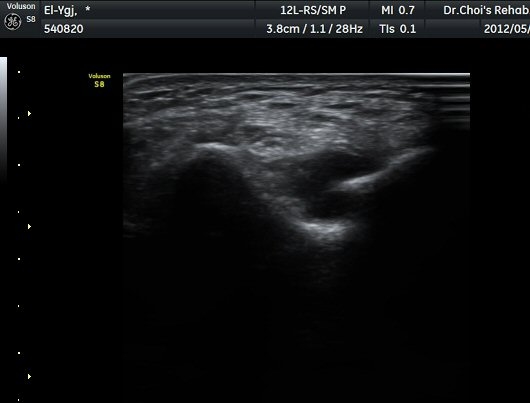

ÁÖ°ü Ⱦ´Ü¸é°Ë»ç¿¡¼­ °üÀý³» ¼ö¾×Àú·ù¿Í ô°ñ½Å°æÀÇ Ç¥ÃþÀ¸·Î ÀüÀ§°¡ °üÂûµÈ´Ù(±×¸² 7).

ÁÖµÎ¿Í È¾´Ü¸é°Ë»ç ¿µ»ó¿¡¼­(»çÁø) ÃÊÀ½ÆÄ À¯µµÇÏ¿¡ °üÀý³» Áֻ縦 ½ÃÇàÇÏ¿´´Ù(µ¿¿µ»ó).